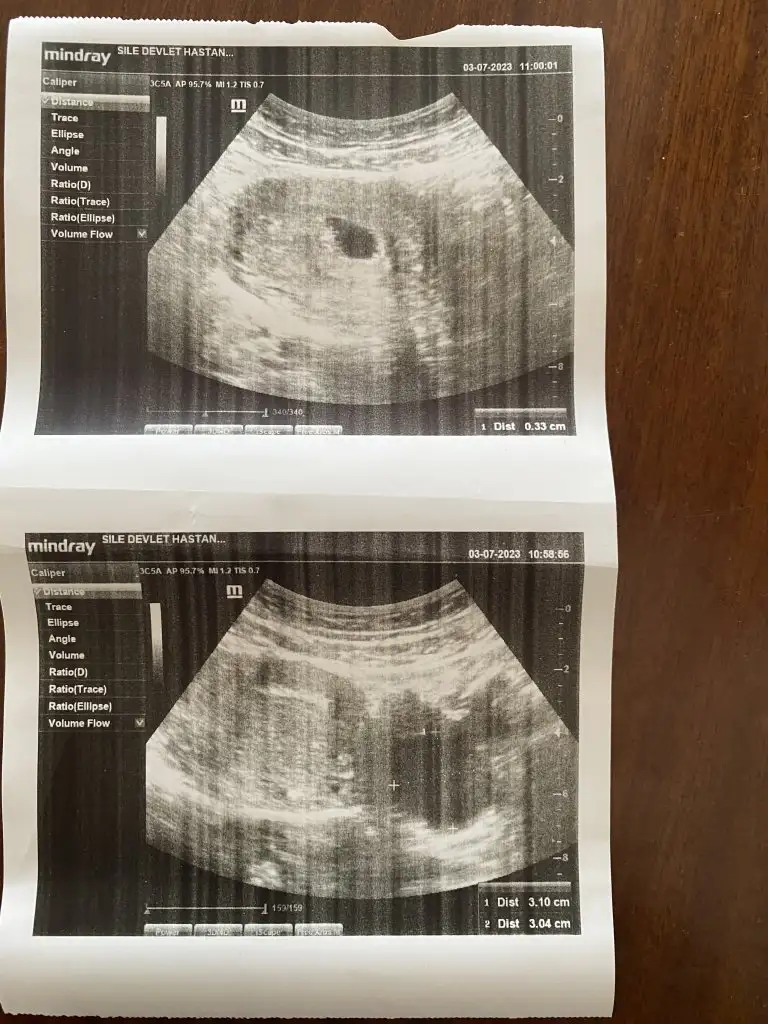

Ben burda 6+4 haftaligim. Karindan. Ultrasona gore 5 haftlik dedi